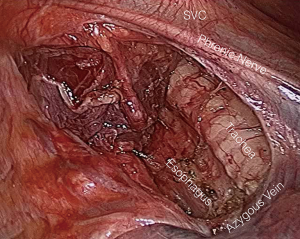

Anterior thoracoscopy and cervical exploration were begun simultaneously. Cervical exploration was performed through a standard transverse collar incision in all cases. Anterior thoracoscopy was performed using three 5-mm ports along the inframammary crease (Figure 3). Visualization and exposure was augmented using carbon dioxide insufflation to a pressure of 8 mmHg. The mediastinal thyroid goiter was easily identified in all cases and exposed by dividing the overlying mediastinal pleura. After mediastinal pleura were opened, sharp dissection was used to separate the goiter from mediastinal structures. Once adhesions to the thyroid capsule were freed, the goiter was delivered bluntly. Vessels were encircled as necessary in order to provide countertraction for goiter dissection. However, gentle traction and manipulation of the goiter alone allows for a safe mediastinal dissection. Care was taken to avoid violation of the thyroid capsule. After all the structures were dissected up to the thoracic inlet, then traction from the cervical incision was applied to pull the specimen through the thoracic inlet safely and under direct vision (Figures 4,5).